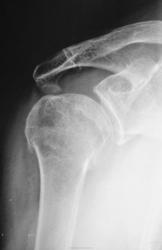

Пол пациента: Мужской пол Тип патологии: Травма Область исследования: Скелетно-мышечная система Методы исследования: Rg Травма. Пациент направлен на рентгенографию плечевого сустава. Ваше мнение уважаемые коллеги? https://radiomed.ru/sites/default/files/styles/case_slider_image/public/user/12/2.p9260006.jpg?itok=ZZgP4cVe https://radiomed.ru/sites/default/files/styles/case_slider_image/public/user/12/3.p9260006a.jpg?itok=SS2b-avQ ID:15657 Пнд, 26/09/2011 - 17:41 #1 Student_Andrew Не на сайте Был на сайте: 13 лет 8 месяцев назад Зарегистрирован: 21.08.2011 - 23:18 Публикации: 106 Вколоченный перелом хирургической шейки правой плечевой кости. Постравматическая гематома в правой аксилярной области(?) Medicus curat, natura sanat Пнд, 26/09/2011 - 20:15 #2 ДокRg Не на сайте Был на сайте: 12 лет 3 месяцев назад Зарегистрирован: 30.03.2011 - 20:05 Публикации: 105 Похоже на патологический.... Пнд, 26/09/2011 - 21:33 #3 Петрович Не на сайте Был на сайте: 7 лет 2 месяцев назад Зарегистрирован: 22.03.2009 - 01:13 Публикации: 3908 Перелом оскольчатый, а возможно, и внутрисуставной. В этом его «патологичность» Неоднозначно всё Втр, 27/09/2011 - 15:13 #4 Катенёв Валенти... Не на сайте Был на сайте: 7 лет 2 недели назад Зарегистрирован: 22.03.2008 - 22:15 Публикации: 54876 Нет, перелом не патологический - рутинный перелом.

Вколоченный перелом хирургической шейки правой плечевой кости. Постравматическая гематома в правой аксилярной области(?)

Похоже на патологический....

Перелом оскольчатый, а возможно, и внутрисуставной. В этом его «патологичность»

Нет, перелом не патологический - рутинный перелом.